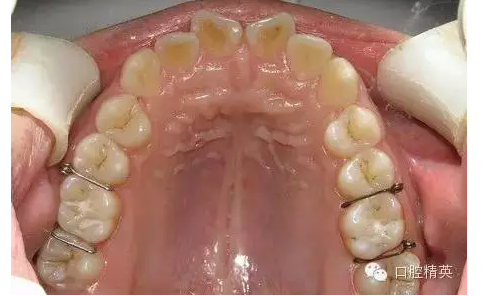

圖1

◆雖然目前正畸臨床上醫(yī)生多用彈力橡皮圈分牙,但當?shù)诙パ雷枭?,與第一磨牙鄰接不良時,或成人第一、第二磨牙鄰接太緊密時以及牙鄰面為面狀接觸的兩鄰牙者,則分牙簧是唯一能解決分牙問題的有效方法;正畸醫(yī)生應作為后備技術熟練掌握其應用技巧。

◆分牙簧各個口腔醫(yī)療器材商都有成品供應,但基本上是圖1形狀,即未激活狀態(tài),正確的使用方法是:在操作前用細絲鉗夾住簧圈處齦臂向內(nèi)彎折,使齦臂末端靠近合臂,形成角度(圖2),分牙時撐開,插入鄰牙間,利用兩臂的剪切彈力,產(chǎn)生間隙。